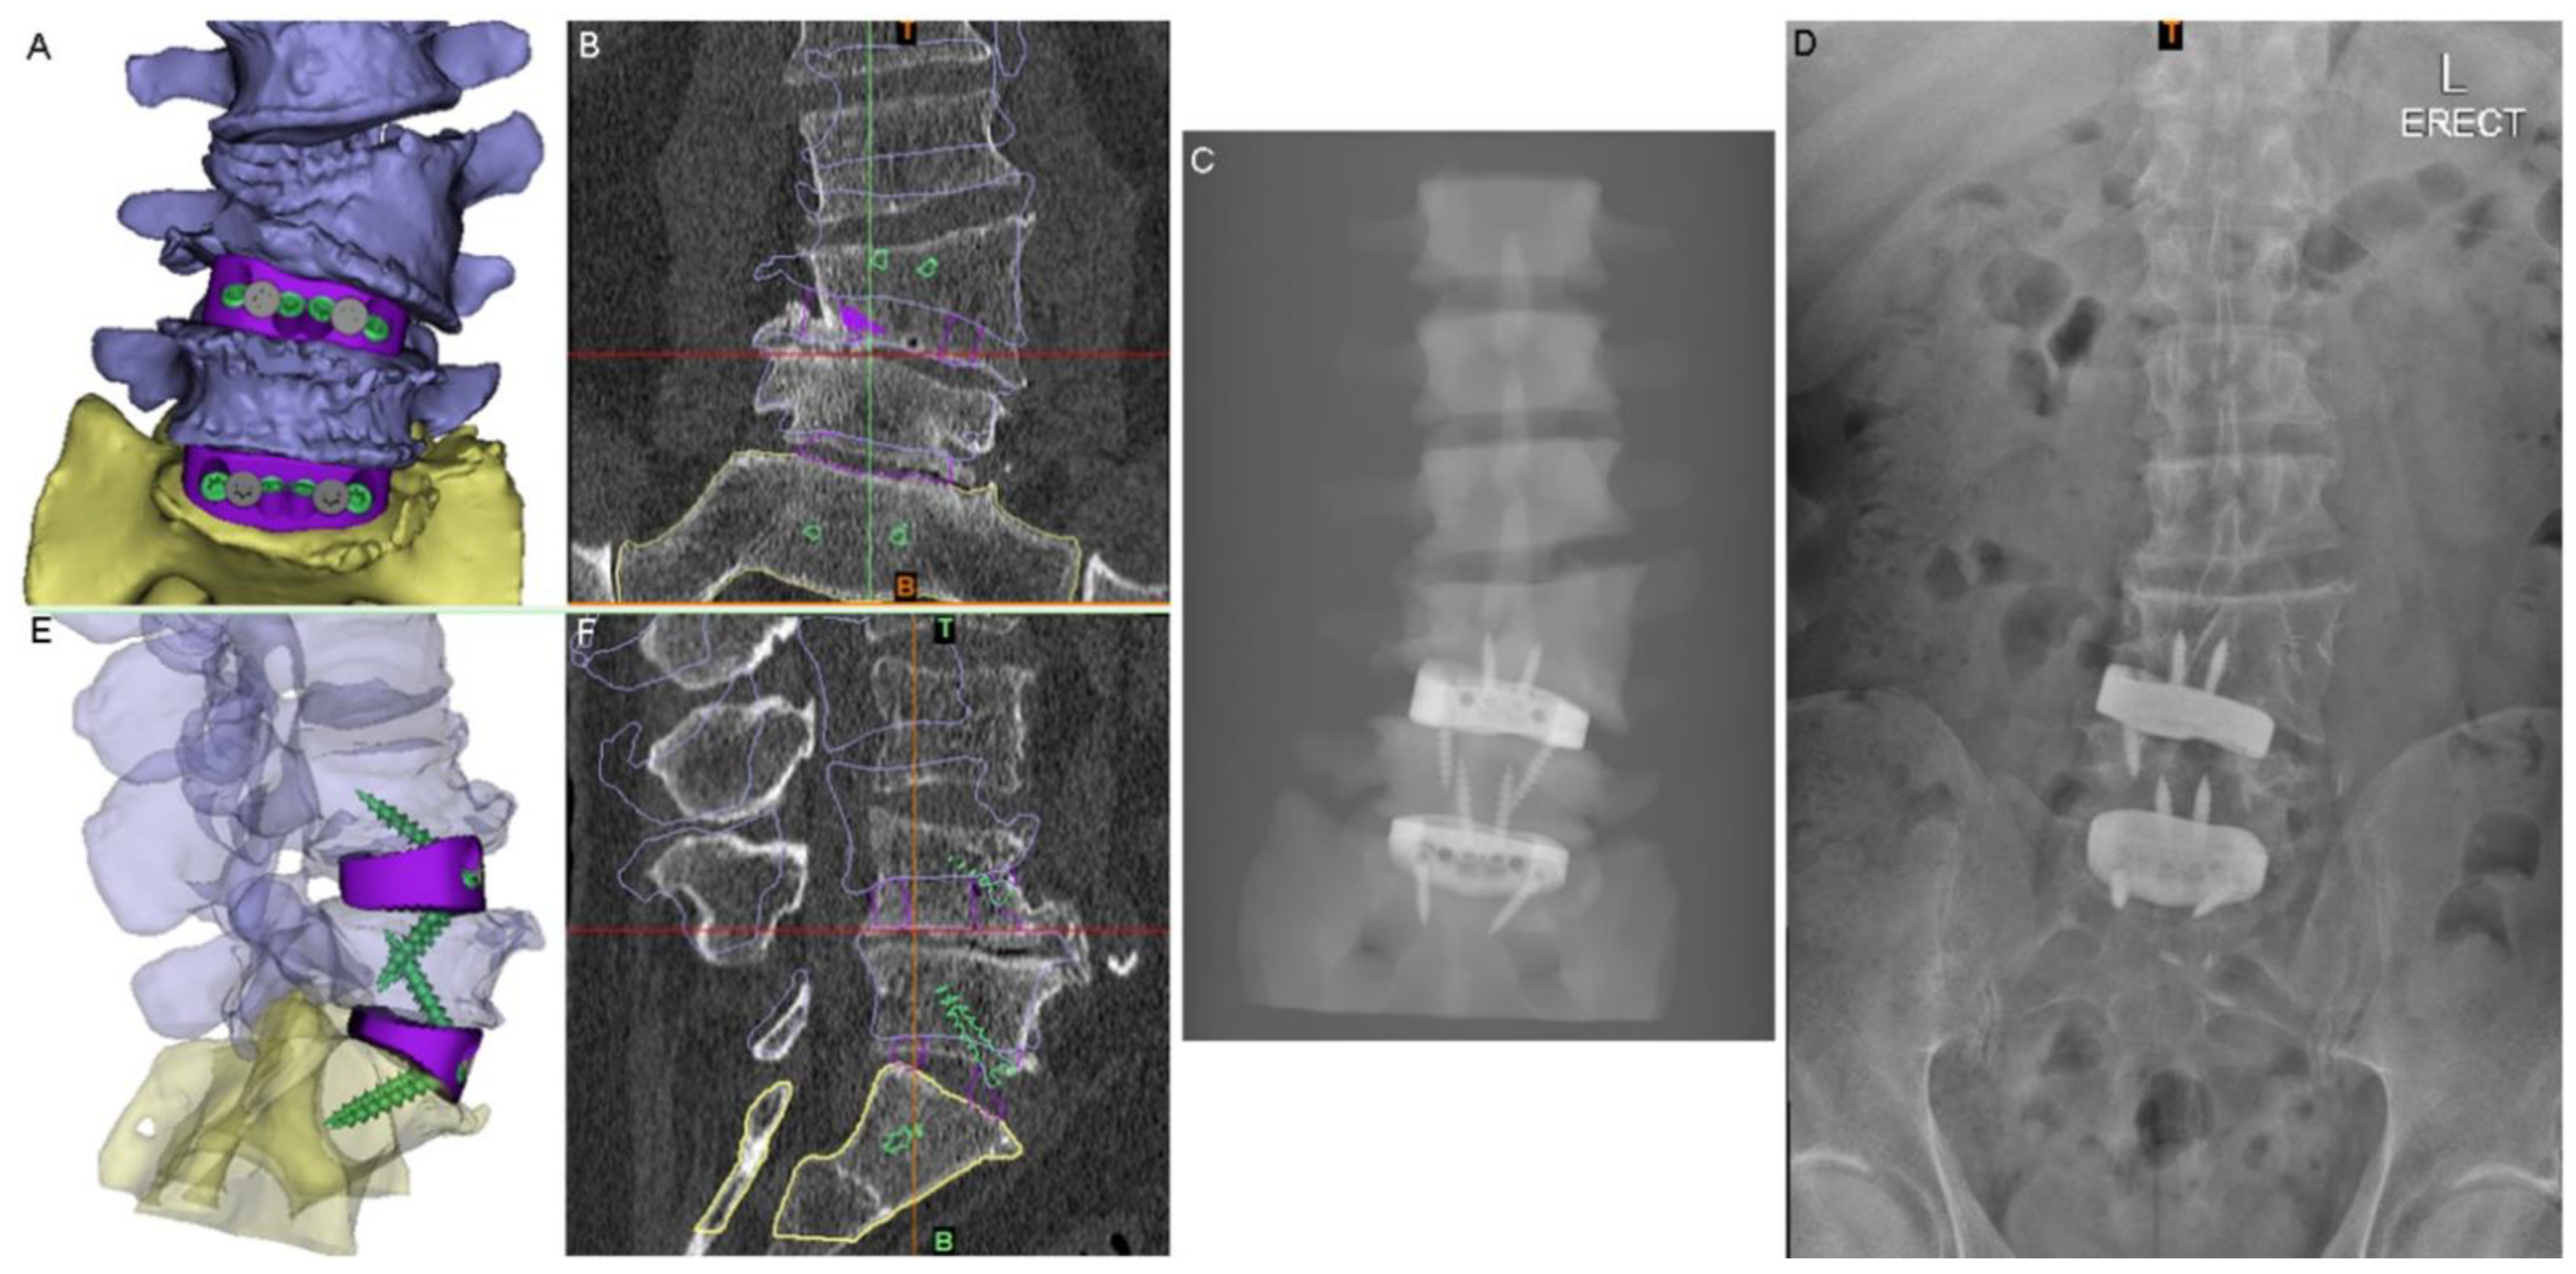

The PSIs were designed using 3DMorphicCAD (3DMorphic Pty Ltd., Sydney, Australia) and Rhinoceros (vs6, McNeel and Associates, Seattle, WA, USA) [22]. Features incorporated included: radiographic alignment assessment features, anti-expulsion teeth, integral screw fixation, variable surface topology/porosity, large central graft window for auto/allograft, pre-planned screw lengths and trajectories (Figure 3), as well as contacting surfaces designed to match the superior and inferior endplate morphologies of each (L4-5 and L5-S1) of the interbody spaces and to correct vertebral alignment in both coronal (scoliotic) and sagittal (lordotic) planes.

Figure 3.

Virtual surgery planning (VSP). (A) Anterior view of the 3D model of the planned anatomical reconstruction and cage positions for medium-sized cages (NB: a small cage was actually used at the L4-5 level). (B) The 3D model shown in (A) superimposed on S1 in the preoperative CT (coronal slice shown). (C) Simulated X-ray of the 3D model in (A). (D) Postoperative standing X-ray. (E) Lateral view of the planned reconstruction with translucent vertebrae to show the screws and devices. (F) Sagittal-plane CT slice with the 3D reconstruction shown in (E) superimposed on S1 to show the planned postoperative state compared to the pathological state.

The close adherence of the relative implant and anatomy positioning in postoperative imaging to the preoperative VSP demonstrates the accurate realisation of VSP correction goals and the validity of this technique (Figure 6). The ability to assess the vascular anatomy preoperatively and refer to the VSP intraoperatively allowed the surgical team to be better prepared, particularly in dealing with the extensive adhesions at the aortic bifurcation, and more rapidly successfully manage the intraoperative aortic tear [8]. The use of prominent osteophytes as patient-specific pathoanatomical landmarks also aided surgical navigation.